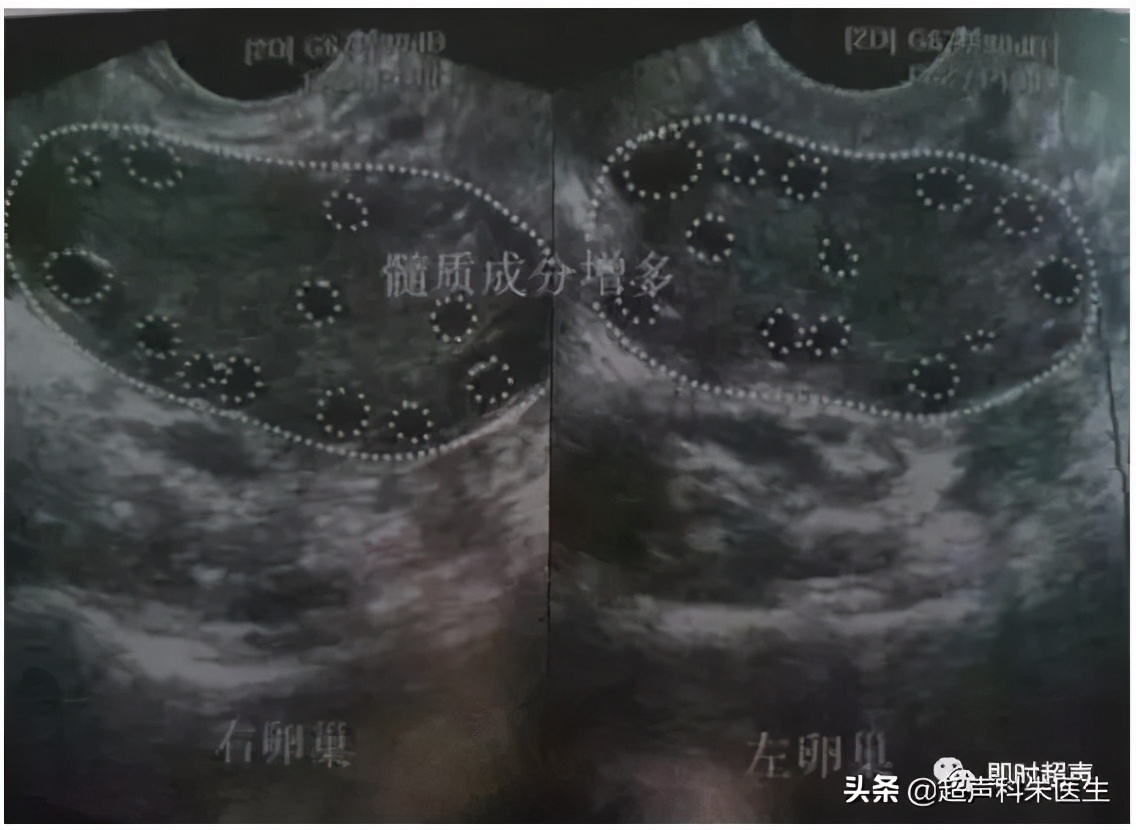

多囊卵巢

卵巢均匀性增大,包膜增厚,回声增强,髓质增多,一侧或双侧卵巢内见>12个直径<10mm的卵泡呈车轮样排列或呈项链征